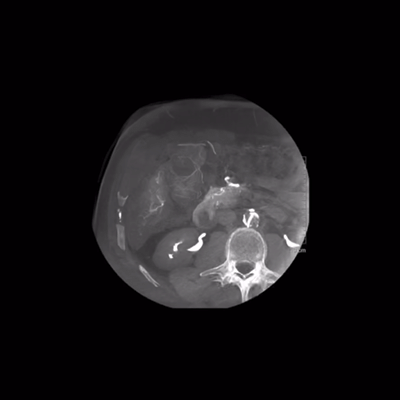

2.5秒扫描全身

ARTIS icono ceiling的最大转速可达95°/s,仅需2.5秒即可获取syngo DynaCT图像,这意味着更少的运动伪影。

图片

图片来源于:西门子医疗官网

Syngo DynaCT是由西门子医疗公司开发的一项医学成像技术。这项技术结合了动态血管成像(Dyna)和计算机断层扫描(CT),旨在提供在介入手术中实时获取高质量3D图像的能力。与传统的术前诊断CT扫描不同,syngo DynaCT专注于动态术中成像,它通过在手术过程中进行快速而连续的图像采集,实现了术中快速的三维与类CT成像。